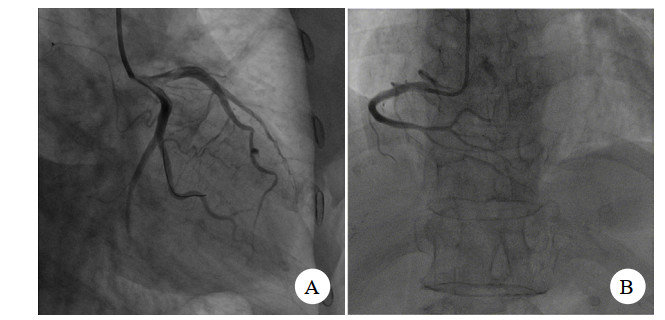

| 图 3 痉挛解除后图像 |

患者冠脉造影提示:①前降支中远端弥漫狭窄80%~90%,第一对角支:全程弥漫狭窄70%~80%,前降支及对角支远端TIMI血流2~3级;前降支逆向有侧支循环提供;②回旋支:近端狭窄85%,回旋支中段闭塞,钝缘支近端闭塞,TIMI血流0级;③右冠状动脉:中段以远闭塞,TIMI血流0级。考虑三支冠脉严脉痉挛。术中予去甲肾上腺素维持下予冠脉内注射硝酸甘油,硝普纳后患者冠脉痉挛解除,冠脉内注入尿激酶原20 mg抗栓,经处理后患者冠脉痉挛解除。